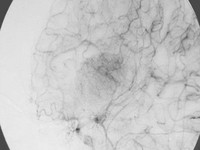

4、磁共振成像(MRI):磁共振成像可清晰显示门静脉及其属支的开放情况,对门-体侧支循环的检出率与动脉-门静脉造影符合率高。磁共振显像可以比较清晰地显示门静脉及其属支的血栓及门静脉的海绵状变形,对肝外门静脉高压的诊断具有重要意义。而神经内科水母头征典型表现为许多细小髓质静脉放射状汇入一条引流静脉,也可表现为髓静脉网散在于引流静脉旁,或仅显示引流静脉而不见髓静脉网。

3、计算机断层扫描(CT):扫描对肝内性及肝外性门静脉高压的诊断均有十分重要的意义。CT扫描不仅可清晰显示肝脏的外形及其轮廓变化,还显示实质及肝内血管变化,并可准确测定肝脏容积。CT扫描图像可明确提示门静脉系有无扩张及各侧支血管的形态变化,注入造影剂之后可显示有无离肝血流。而神经内科水母头征平扫常显示不清,常无周围脑水肿表现,有时可见出血等改变。增强扫描,特别是CT血管造影时,典型表现为许多细小髓质静脉放射状汇入一条或数条引流静脉,最后汇入静脉窦。